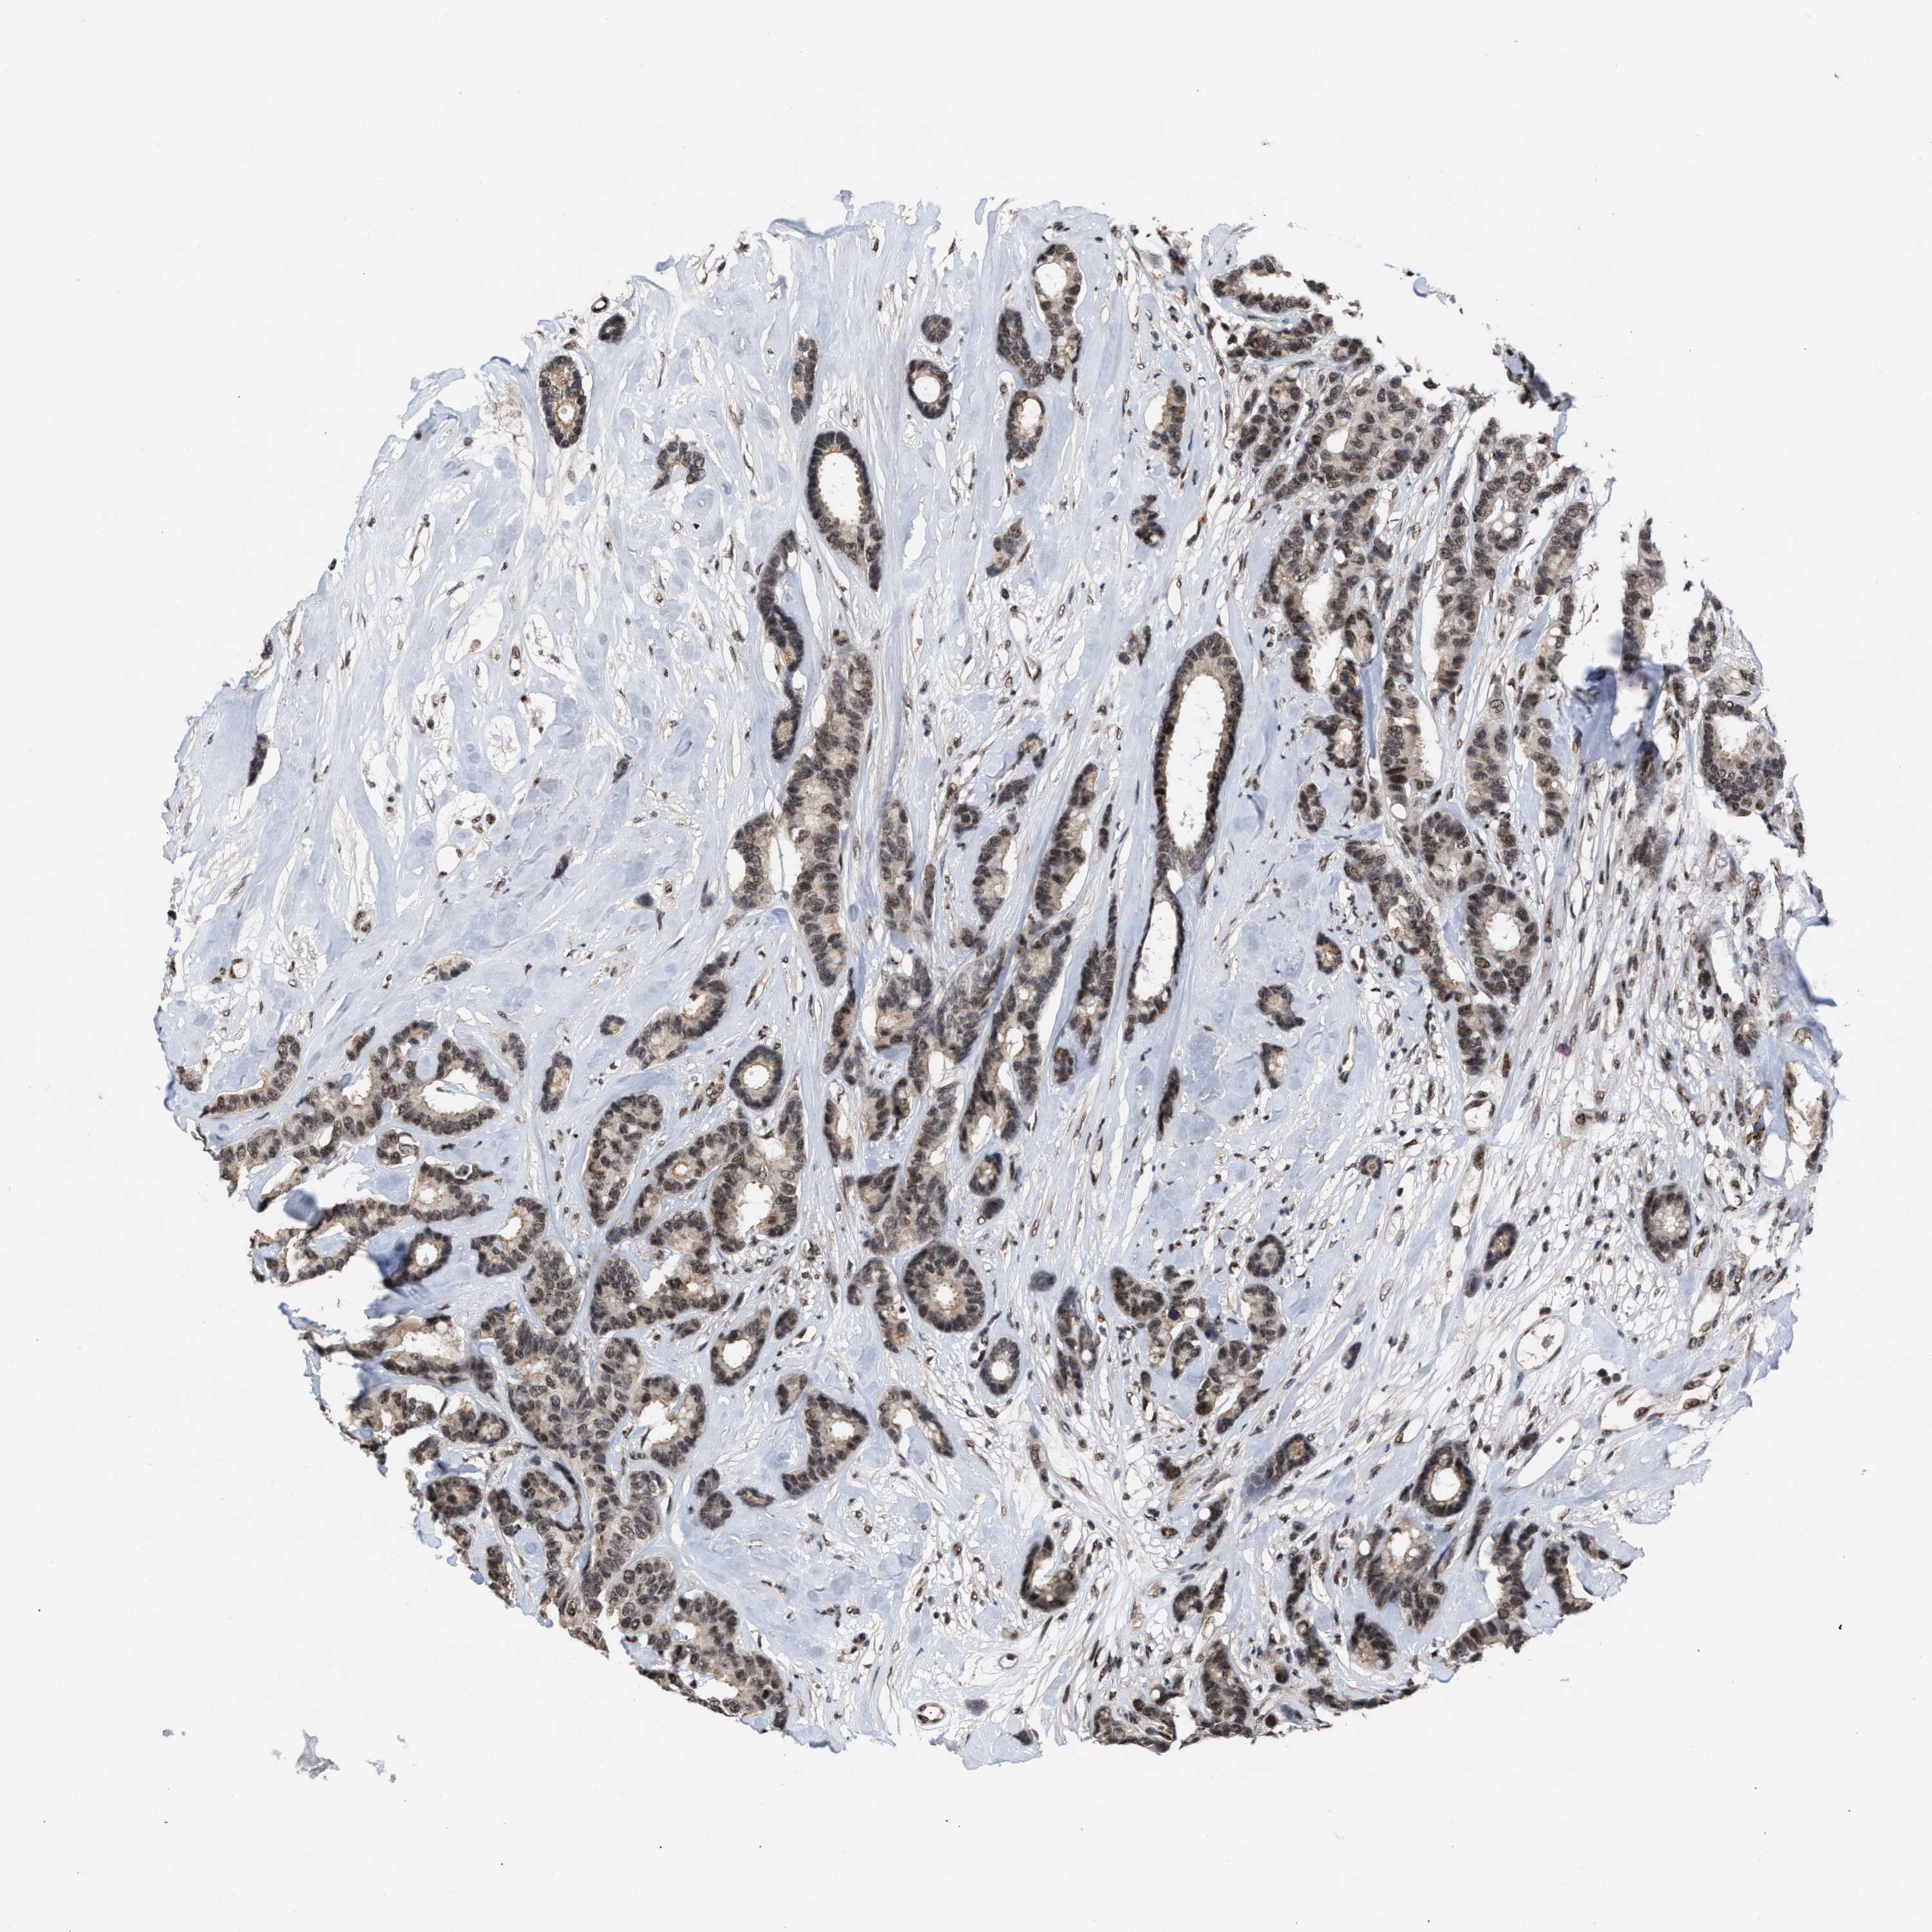

BRCA TCGA BRCA VALIDATION PROTEIN EXPRESSION

ANTIBODIES

AND

VALIDATION